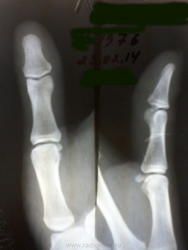

Прищемила палец дверцей машины, внешне изменения не выражены, только болит - есть перелом?

Мне наоборот, кажется, что есть продольный перелом ногтевой фаланги. Качество не очень, поэтому на точность не претендую.

Видимо, Вы это просветление имели ввиду? Сомнительно. Контур гладкий. Послушаем, что скажет большинство.

Добавлю тогда свой взгляд и я.)

Поперечный надлом (неполный такой перелом) лучевого края основания ногтевой фаланги. И пусть боги с таким качеством опровергают и низвергают меня!)) Я - Никто, мне можно, простительно!))

+yesПо Muller - частичный суставной.

Есть ещё чёткость и гладкость контуров, если это добавочная кость. Или, напротив - неровность и нечёткость контура при переломе. Как правило, костный фрагмент имеет "гнездо", откуда он отошёл. На мониторе таких тонкостей мне не увидеть, Вам в натуре проще.

Спасибо всем за мнения, сама н\ф по снимку норма. Написала краевой основания, посчитала, что оторвался из участка просветления в основании н\ф. А атласа под рукой не было. Мне важно попадание в "десятку", так что совет из поста № 7 не очень подходит. Теперь уже что сделано, то сделано.

А лучевой контур фаланги Вас совсем не напугал, да?.. Надеюсь, на контроле он не изменит своего поведения.